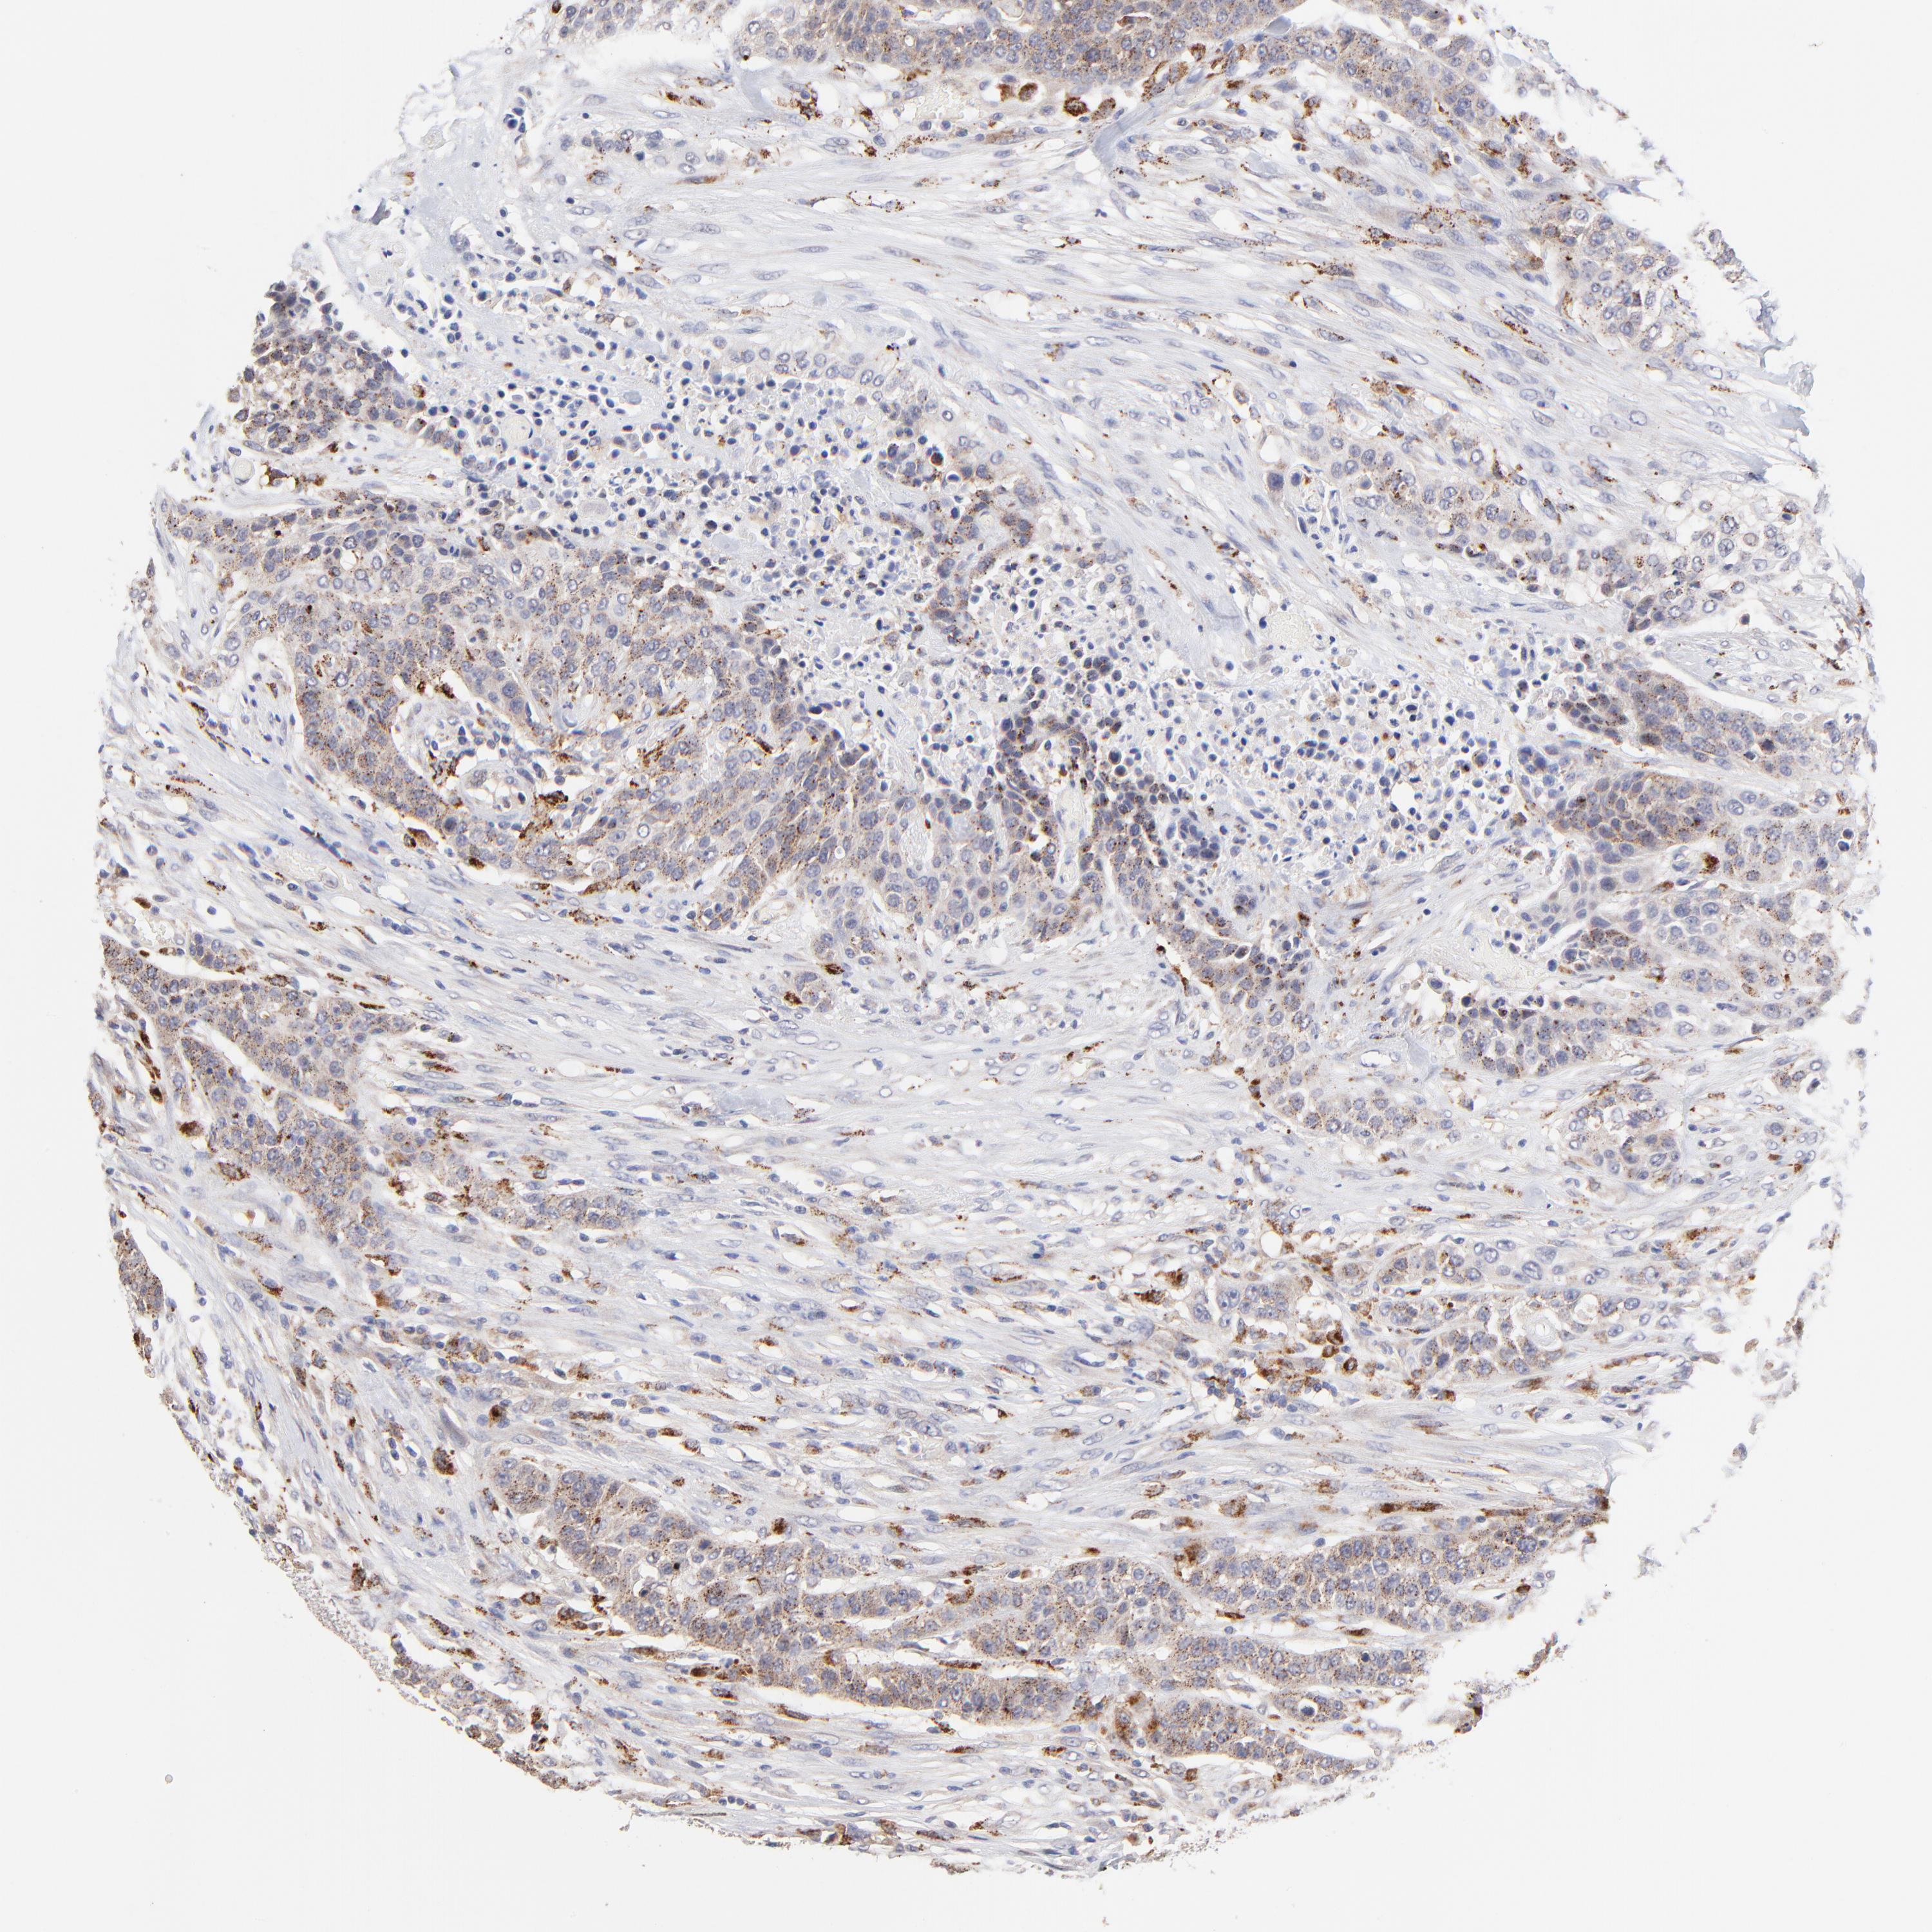

UROTHELIAL CANCER - Protein expressioni

A mouse-over function shows sample information and annotation data. Click on an image to view it in a full screen mode. Samples can be filtered based on level of antibody staining by selecting one or several of the following categories: high, medium, low and not detected. The assay and annotation is described here.

Note that samples used for immunohistochemistry by the Human Protein Atlas do not correspond to samples in the TCGA dataset.

Antibody stainingi

Antibody staining in the annotated cell types in the current human tissue is reported as not detected, low, medium, or high, based on conventional immunohistochemistry profiling in selected tissues. This score is based on the combination of the staining intensity and fraction of stained cells.

Each image is clickable and will lead to virtual microscopy that enables deeper exploration of all samples and also displays staining intensity scores, fraction scores and subcellular localization as well as patient and tissue information for each sample.

Antibody HPA003005

Staining

High

Medium

Low

Not detected

Intensity

Strong

Moderate

Weak

Negative

Quantity

>75%

75%-25%

<25%

None

Location

Nuclear

Cytoplasmic/membranous

Cytoplasmic/membranous,nuclear

Urothelial carcinoma, High grade

Urothelial carcinoma, Low grade